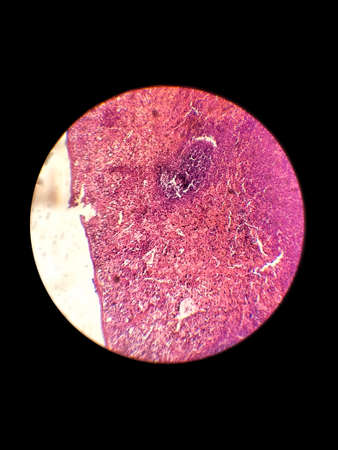

Biological histological fixed colored preparation of the spleen - a secondary organ of the immune system